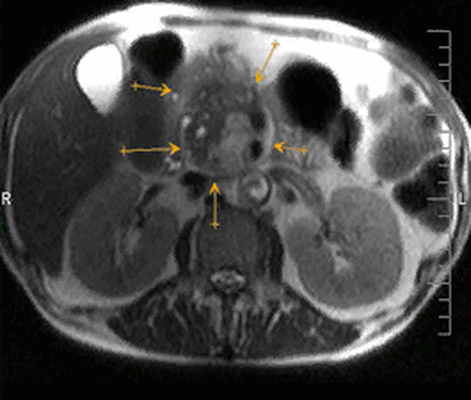

МРТ с контрастом, коронарная плоскость: протоковая карцинома головки поджелудочной железы, прорастание в брыжейку тонкой кишки (стрелки)